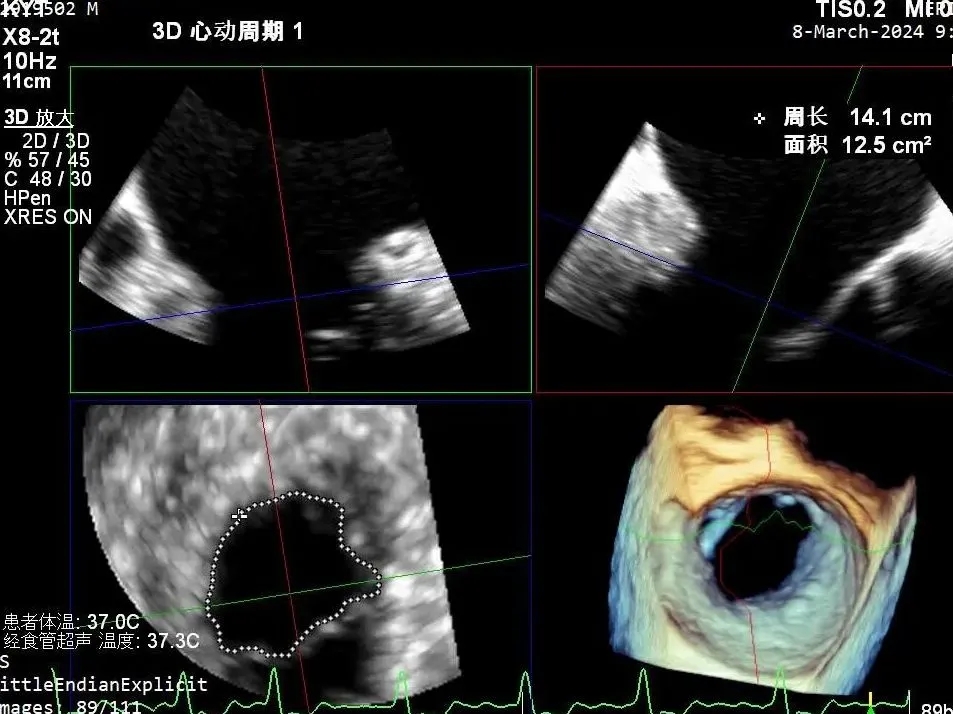

超声心动图:

二尖瓣后叶活动受限,呈房源性栓系,以P3区为重,二尖瓣前叶假性脱垂,二尖瓣瓣环前后径49mm,左右径40mm。

PISA法测r=12mm,EROA=0.72cm2,RVOL=100ml,RF 26%。LVEDD 57mm,左房71*59*77mm,右房55*69mm,LVEF 70%。

超声提示:

二尖瓣反流(重度,4+级,Carpentier I型)

三尖瓣反流(轻度)

主动脉瓣反流(轻度)

双房及心耳内未见确切血栓回声